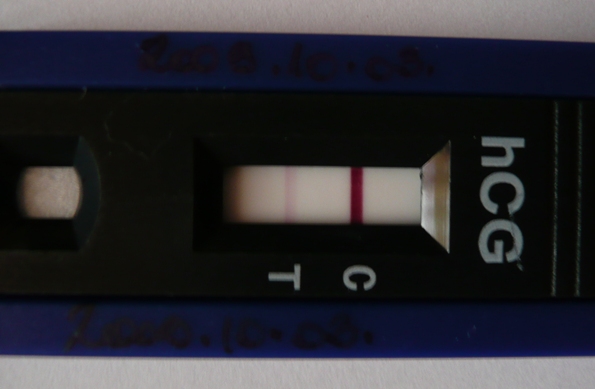

Nem hiszek a szememnek

! PRINCZIKE

ÓRIÁSI GRATULA neked

Gyönyörű a babókád! Mit éreztél a pozi teszt láttán?